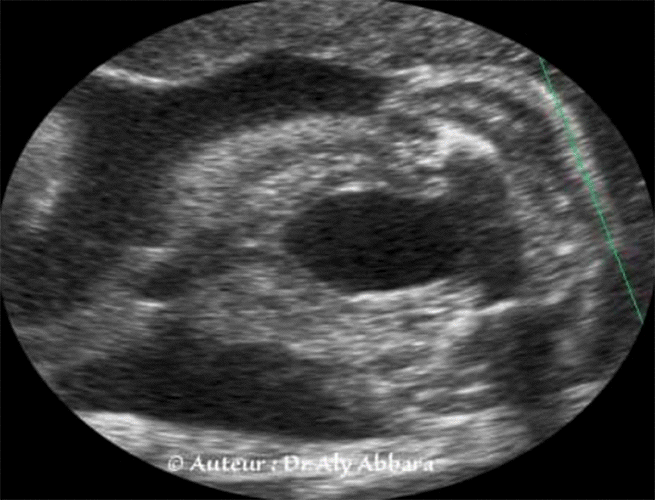

Série de coupes axiales centrées sur la vessie et montrant le trajet habituel des deux artères ombilicales (branches des artères iliaques internes) qui encerclent la vessie latéralement, puis elles rejoignent le cordon ombilical au niveau de l'ombilic.

Cette coupe permet de diagnostiquer facilement la présence de l'artère ombilicale unique et de déterminer le côté dans lequel l'artère ombilicale est manquante.

Le diagnostic échographique est possible par la réalisation d'une coupe transversale sur le cordon ; l'utilisation du Doppler couleur facilite ce diagnostic. Pour déterminer le côté de l'artère absente, il faut réaliser une coupe transversale au niveau de la vessie, sur cette coupe, le Doppler couleur met en évidence l'artère ombilicale manquante.